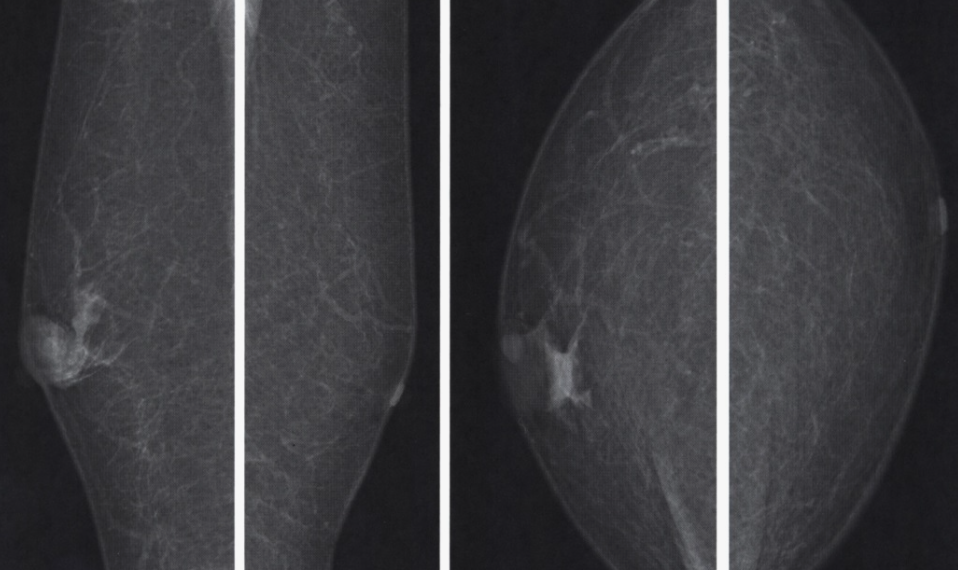

medicalplanet.su

В соцсетях уже гуляет хайповая версия: «ОСМС потеряло страх, мужчин отправляют на маммографию…» — звучит эффектно, но, как пояснил генеральный директор «Олимп» Ерлан Сулейменов, в этом нет никакого массового абсурда, сообщает SHYNDYK.KZ.

«Да, мужчины действительно проходят маммографию, и это не ошибка. Есть такой диагноз гинекомастия. Простым языком, в норме в грудной области должен быть жир, а не железа. Но, к несчастью, у некоторых мужчин тоже бывает железистая ткань. Если она появляется ― это уже тревожный сигнал», ― сказал он.

Сулейменов отметил, что маммография назначается мужчинам по строгим медицинским показаниям:

• при семейной истории рака молочной железы;

• при мутациях генов BRCA;

• при симптомах вроде уплотнения, асимметрии или выделений из соска.

«В ряде исследований маммография у мужчин из группы высокого риска выявляла рак чаще, чем у женщин со средним риском», — добавил он.

Гендиректор подчеркнул, что 619 мужчин за два года — это далеко не «медицинский беспредел». Это может быть нормальной статистикой, следствием реальных показаний или единичными случаями, требующими разбирательства.

«Нарушения, безусловно, бывают, но с этим нужно работать точечно. Медицина — это не «всё плохо» и не «всё хорошо». Лечить нужно не болезнь, а человека с болезнью», — подытожил Сулейменов.